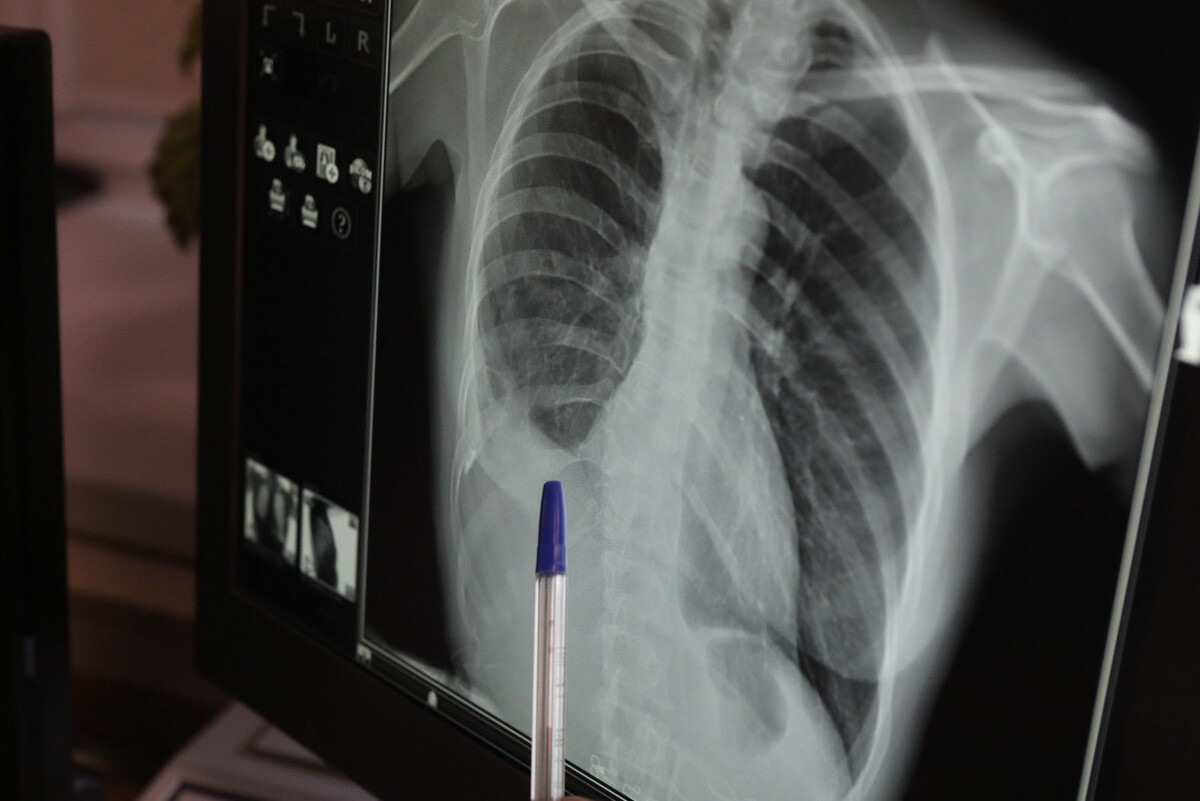

Прокуратура Невского района инициировала принудительную госпитализацию четырех жителей Петербурга, заболевших туберкулезом. В пресс-службе прокуратуры Санкт-Петербурга сообщали, что в ходе проверки соблюдения законодательства, касающегося охраны здоровья населения, было установлено, что четырем гражданам необходима специализированная терапия в противотуберкулезном стационаре. Однако они уклонялись от лечения, что представляло реальную угрозу для здоровья окружающих. В защиту интересов неопределенного круга лиц прокурор района подал иск в суд о принудительной госпитализации этих граждан в противотуберкулезное учреждение. Суд удовлетворил требования прокуратуры в полном объеме. В настоящее время заболевшие госпитализированы для обязательного обследования и лечения. Ранее сообщалось, что суд взыскал с дроппера 100 тысяч рублей, похищенных у петербургской пенсионерки.